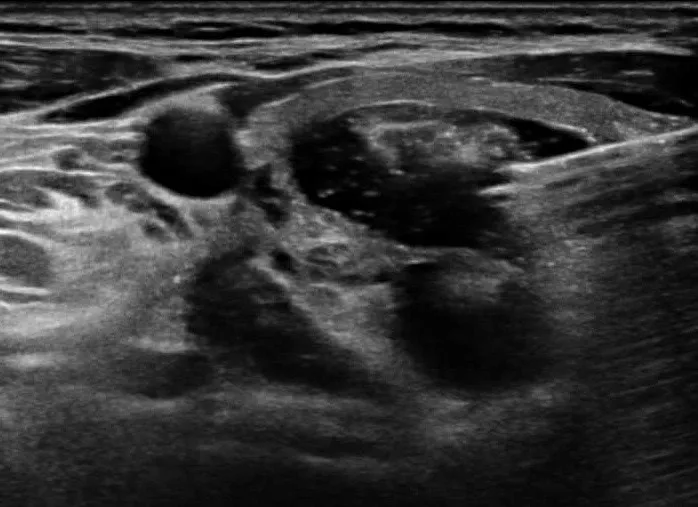

암이 아닌 종양을 양성종양이라 하며, 갑상선 초음파에서 발견된 결절에 대해 세포검사를 시행했을 때 악성 소견이 확인되지 않으면 갑상선 양성종양으로 분류합니다.

갑상선 양성종양은 생명을 위협하는 경우가 드물어 반드시 치료가 필요한 것은 아닙니다. 다만 결절이 상당한 크기로 커질 경우, 외형적으로 눈에 띄거나 음식을 삼킬 때 이물감이 생기거나, 기도를 눌러 호흡에 불편함을 초래할 수 있습니다.

이런 증상이 나타나면 양성이더라도 치료를 고려해야 합니다. 또한 증상이 뚜렷하지 않더라도 추적 관찰 중 크기가 빠르게 증가하고 있다면, 더 커지기 전에 미리 치료를 받는 것이 바람직합니다.

갑상선에 생긴 비정상적인 혹(종괴, 종양)을 갑상선결절이라고 부릅니다.

갑상선결절의 90% 이상은 양성결절(양성종양)으로 악성결절(갑상선암)과 달리

생명에 지장을 주지 않습니다.